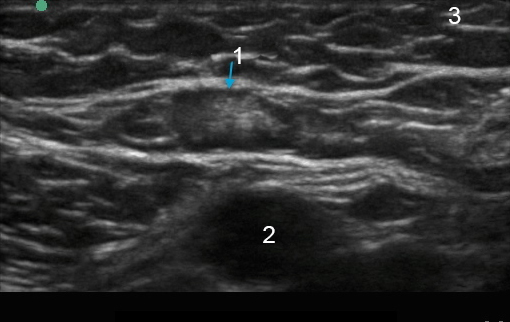

Imagen axilar de ganglio linfático de tejido mamario

Ganglio linfático

Arteria

Tejido mamario